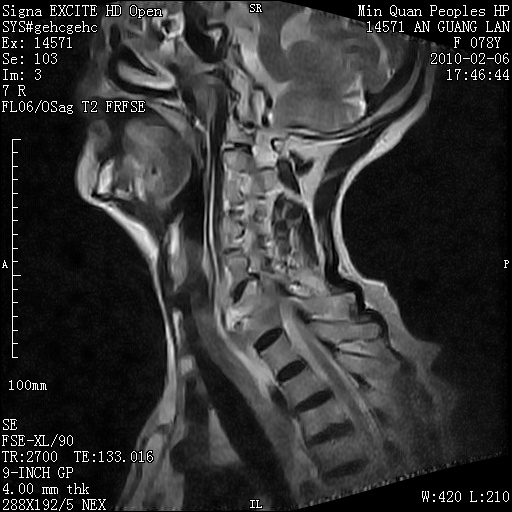

标题: MRI2763:C6、C7椎体病变性质?

f,78y,颈部与双上肢阵发性剧痛40余天。ct可见c6、c7椎体虫蚀样破坏,其间椎间隙变窄(没有图片资料可供上传)。

考虑椎体结核并椎旁脓肿。

支持 c6、7椎体结核并椎旁冷脓肿形成。